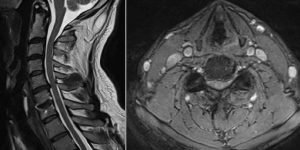

Paciente varón 45 años, operado hace 2 años artrodesis C6-C7. Acude por presentar dolor cervical y persistencia de hormigueo y acorchamiento en miembro superior izquierdo, sobre todo en segundo y tercer dedos. El acorchamiento no desapareció tras la primera cirugía. Se solicita una resonancia magnética de columna cervical y un electromiograma.

RMN Columna Cervical: Cambios postquirúrgicos con material de fijación. Hernia discal C5-C6.

Hernia discal C5-C6, material de fijación C6-C7

Electromiograma: Cambios denervatorios crónicos en miotoma C7 izquierdo

Paciente presenta síndrome de nivel adyacente, es decir el disco inmediato superior a la cirugía previa se lesiona produciéndose la hernia discal. Tras las pruebas se decide reintervenir al paciente. En este caso consideramos que la artrodesis percutánea de columna cervical con D-TRAX es la mejor opción quirúrgica. Al abordar el problema por vía posterior evitamos la fibrosis de la primera cirugía. También evitamos la posibilidad de lesionar estructuras nerviosas importantes. Además la recuperación del paciente será más rápida.